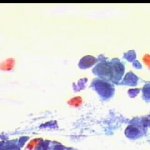

Εικονες φυσιολογικών και παθολογικών κυττάρων ενδοτραχήλου κι ενδομητρίου στο επίχρισμα κατά Papanicolaou. Περιστατικά ιατρείου. Παρατίθενται για τις ανάγκες επίδειξης περιστατικών στο forum του www.gyn.gr, για φοιτητές εργαστηριακών παραϊατρικών επαγγελμάτων και για καθε άλλο ενδιαφερόμενο.